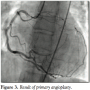

Intracoronary bolus of IIb/IIIa eptifibatide was given and followed by intravenous infusion. Surprisingly, the patient’s hemodynamics were only slightly compromised — she presented with pulmonary congestion (but not pulmonary edema), arterial blood pressure remained normal throughout the angioplasty, and no cardiac support was required (Figures 4, 5, and 6).

After the procedure was completed, the patient developed transient proximal second-degree atrial-ventricular block that required no action. Accompanying urinary infection was successfully treated with antibiotics. Further cardiac rehabilitation was uneventful. ECG showed typical evolution of inferior wall myocardial infarction. After 40 days, she

was readmitted to our hospital for repeat angiography. Good short-term angiographic result of angioplasty was confirmed.

On the control angiography, it was apparent that the patient had single coronary vessel that originated in the right sinus of Valsalva. The LM ostium was absent. The single artery showed a typical course of a dominant RCA and created branches to the circumflex artery (LCX) and the left anterior descending (LAD) branch. The secondary vessels clearly branched toward the base of the heart and they showed no significant arteriosclerotic lesions. Echocardiography found no concomittant

structural heart anomalies. After 9 months, the patient remained asymptomatic and the early submaximal exercise ECG test was negative. Magnetic resonance imaging (MRI) confirmed both absence of LM and presence of single coronary artery (SCA) originating from the right sinus of Valsalva (Figure 7).